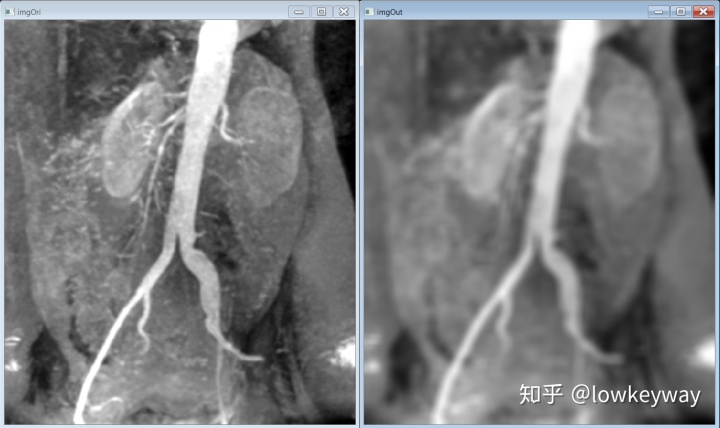

运行结果:

58fa61fb0b9325e08bfc7b615b0eacdf.png

跟教材中的一模一样

a4784b9fbdd4318600e0e700529e675b.png

打完收工?总感觉有点意犹未尽。在code的时候发现邻域算子的大小设定对处理结果起决定性的作用,要是有什么办法可以直观的看到就好了。不如用滑动进度条来。